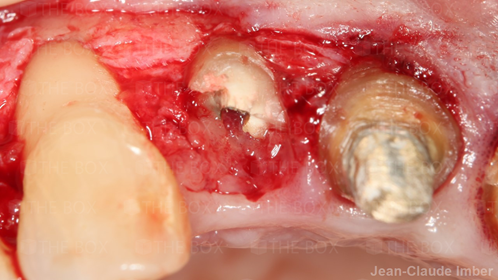

A new case was made public by Jean-Claude Imber check it out here.